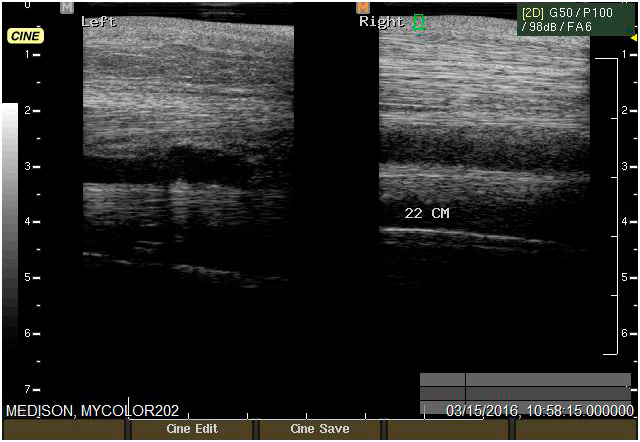

Ecografía

Cuenta con Ecografía digital de alta complejidad.

17 años de experiencia siendo una de las ecografistas más reconocidas en la práctica de equinos. Realiza pasantías en la universidad de Davis California y en Mid-Atlantic Equine Medical Center en New Jersey.